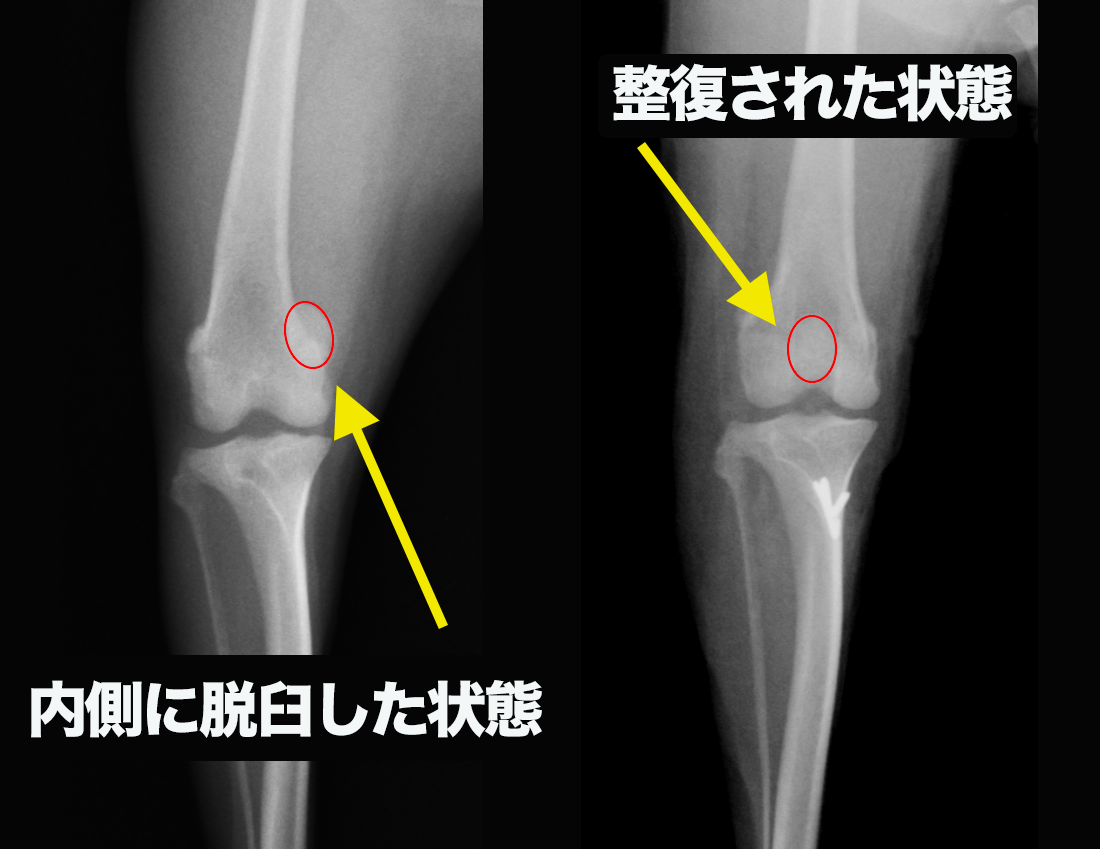

診断

診断は、まず触診による整形外科学的検査が基本となります。

膝蓋骨がどの方向に、どの程度外れるかを評価し、グレード分類を行います。

画像検査として、レントゲン検査を行います。

重症例や骨変形が重度の症例では、大腿骨・脛骨を含めた撮影が必要となり、必要に応じてCT検査により三次元的に変形を評価します。